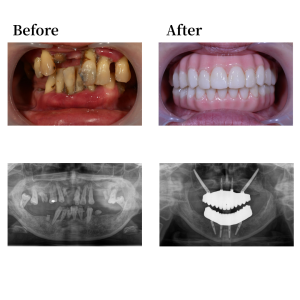

背景

患者談。歯がグラグラで本数も少なく、見た目の悩みや「入れ歯にはしたくない」という強い思いから、解決策を求めて来院されました。HPやYouTubeをきっかけに当院を知り、それまでオールオン4という治療法についてはご存知ありませんでした。

既往歴に十二指腸潰瘍がありますが、現在は非喫煙者で飲酒も週1〜2回程度です。理事長より上顎ザイゴマ2本を併用するオールオン4の提案を受け、治療を決定。オペの仕上がりに非常に満足されており、「悩んでいる人がいたらぜひ勧めたい」とのお言葉をいただいています。

インプラント詳細

上顎骨の形状を整え、12,22の位置にノーマルインプラントを0度垂直埋入。15, 25 の位置にノーマルインプラントを30度傾斜埋入。下顎も形状を整え、45, 42, 32, 35の位置にそれぞれオールオン4インプラントを埋入。 42, 32の位置に、0度垂直埋入、45, 35の位置に17度傾斜埋入。その後、マルチユニットアバットメントで角度補正を行い、プロビジョナルレストレーション(審美的な仮歯)を装着した。

上部構造詳細

上下顎はUTジルコニアで構成された、フルジルコニアブリッジでファイナルレストレーションとした。焼成されたジルコニアはステインテクニックで着色した。シェードカラーはA1。